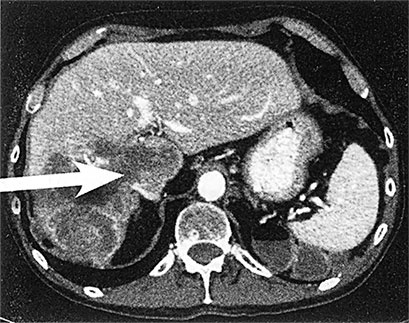

Но такой взгляд на рак на молекулярном уровне не является единственным полезным инструментом в подборе лечения. Для меня рак (рис. 4) выглядит примерно так:

А. Печень человека с метастазами рака толстой кишки

Б. Аксиальная компьютерная томография, показывающая наличие метастазов рака в печени

Вот мы видим А – печень с раком толстой кишки, что правильнее назвать «метастазы рака толстой кишки в печень». Рак переместился, метастазировал, из толстой кишки в печень, что подтверждается белыми образованиями на снимке. Б – томограмма другой печени, пораженной раком толстой кишки («метастазы рака толстой кишки в печень»). Обратите внимание на пять круглых темных образований в левой части изображения. И В – изображение рака толстой кишки в лимфоузле под микроскопом («метастазы рака толстой кишки в лимфоузел»). Пояснение: «рак толстой кишки», который метастазировал в легкие, не будет называться «рак легких». Это все еще рак толстой кишки и выглядит он как рак толстой кишки.